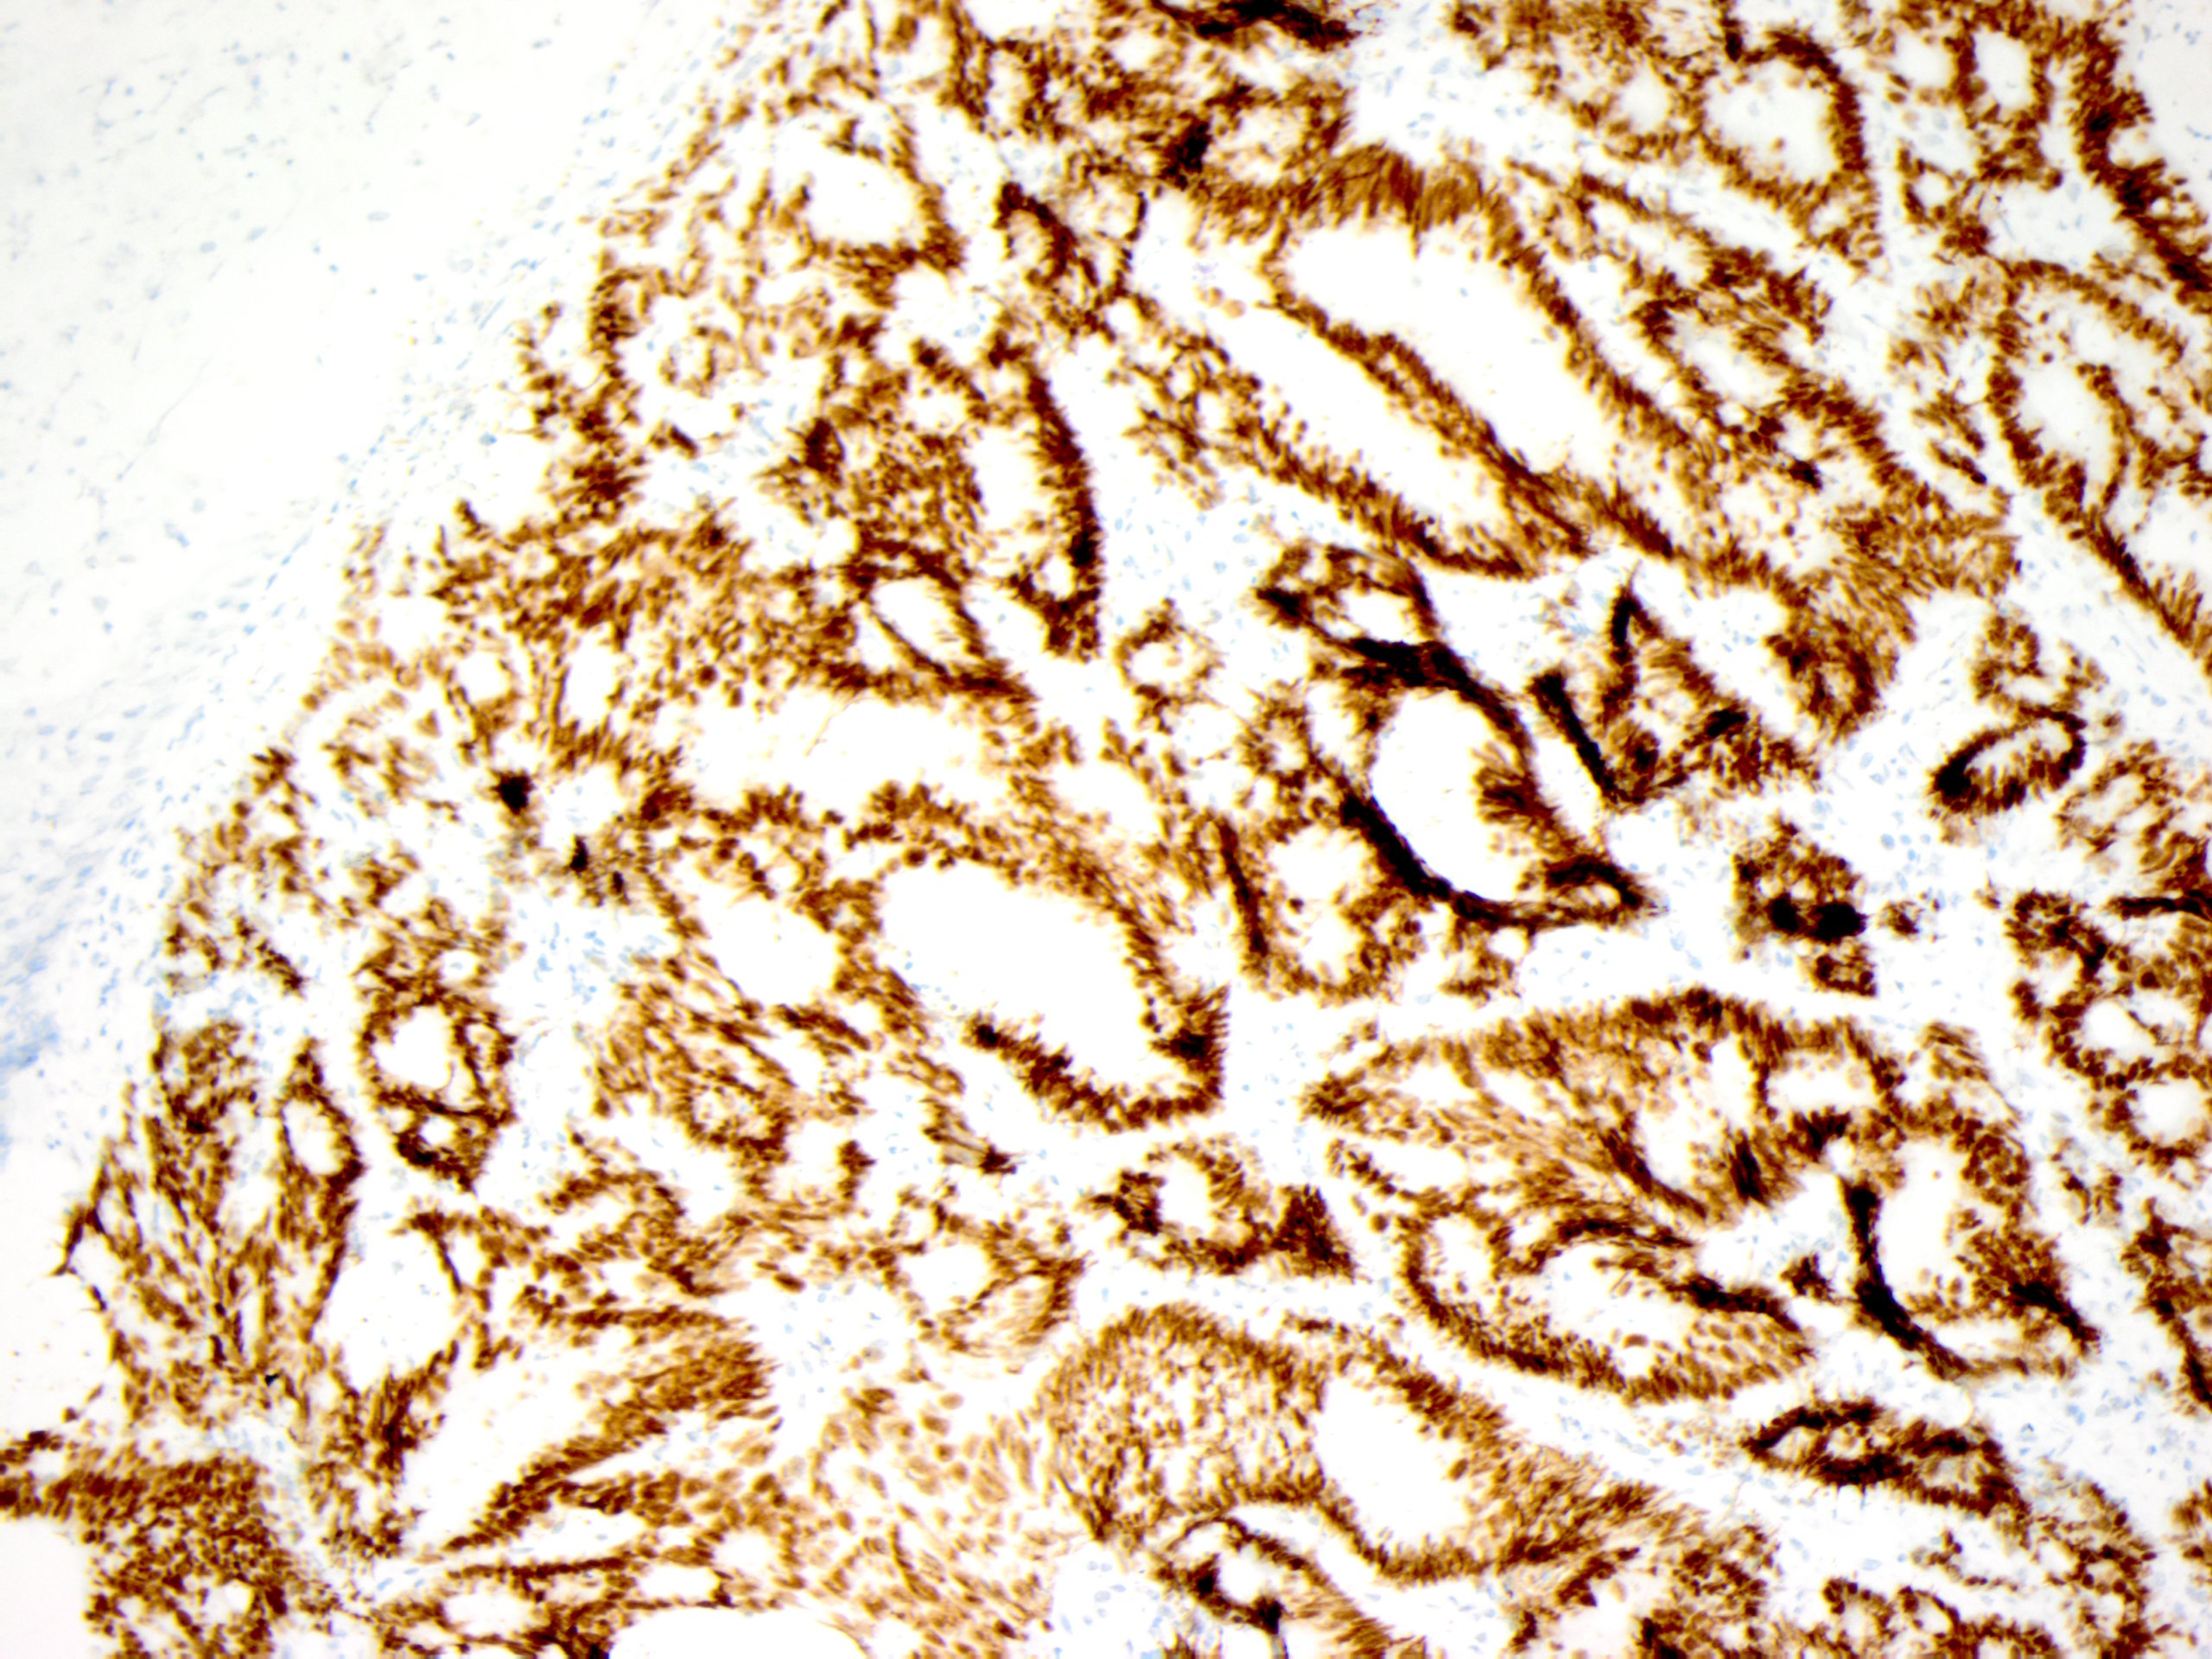

A biopsy of the skin lesion is performed and reveals squamous epithelium overlying a dermal-based infiltrative malignant gland-forming neoplasm composed of irregular glands (Figure 2). Immunohistochemical analysis reveals the cells of interest are positive for CK20 (Figure 3) and CDX2 (Figure 4), while negative for TTF-1 and PAX-8. The morphologic and immunophenotypic findings are consistent with a cutaneous metastasis from a gastrointestinal tract primary.